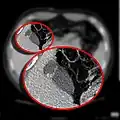

The Phrygian cap results from folding of the gallbladder fundus.

In medicine, a Phrygian cap is the folded portion of some gallbladders that resembles the Phrygian cap (a soft conical cap with the top pulled forward, associated in antiquity with the inhabitants of Phrygia, a region of central Anatolia). It is a normal anatomical variant seen in 1-6% of patients.[1] It is caused by a fold in the gallbladder where the gallbladder fundus joins the gallbladder body.[2] Apart from the chance of being mistaken for stones on a sonogram, it has no other medical implications nor does it predispose one to other diseases. However, due to potential decrease in bile flow, it may warrant a preventive removal of the gallbladder.